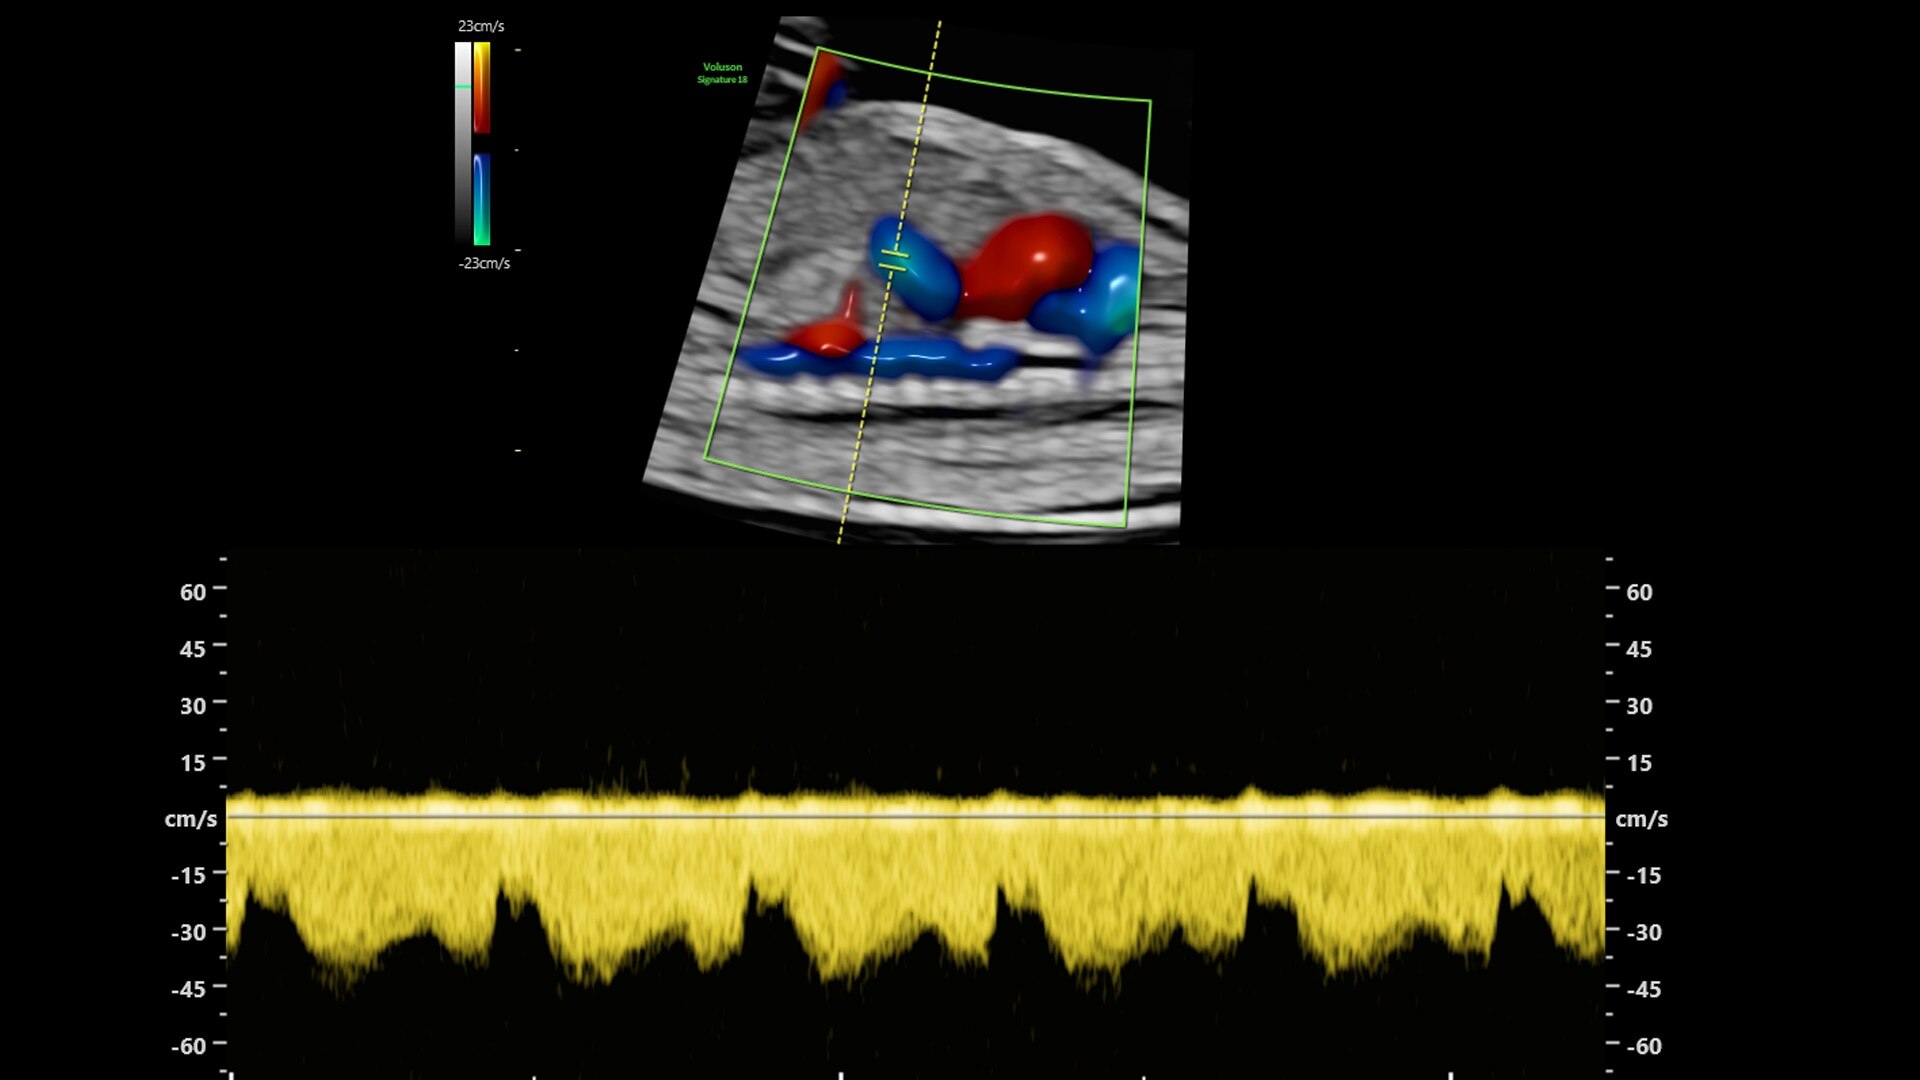

Fast, easy 3D-like blood flow visualization

Next level color Doppler delivers exceptional sensitivity for easy, fast visualization of blood flow, revealing even the tiniest vessels.

3-radiantflow-clinical-image-ci-en